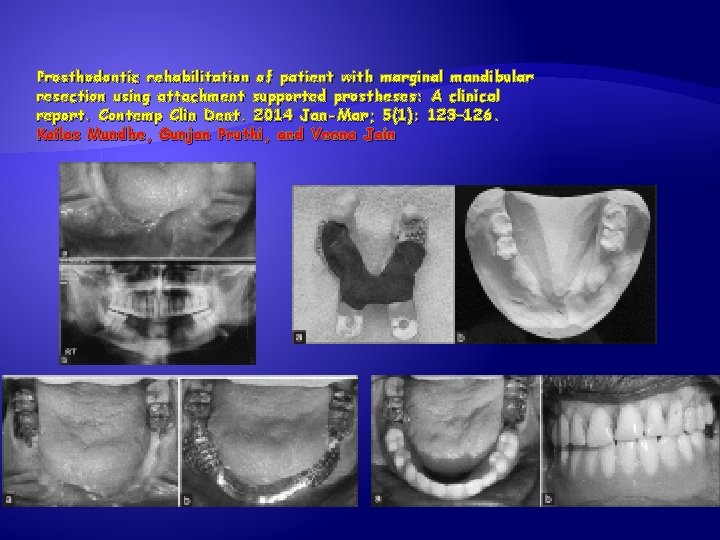

Prosthodontic rehabilitation of patient with marginal mandibular resection using attachment supported prostheses: A clinical report. Contemp Clin Dent. 2014 Jan-Mar; 5(1): 123– 126. Kailas Mundhe, Gunjan Pruthi, and Veena Jain